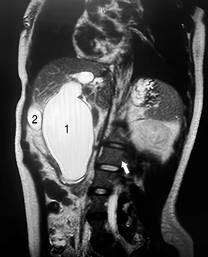

Figura 3: Colangiografía por resonancia magnética. Corte coronal de colangioresonancia magnética; (1) quiste de colédoco (70 mm) con zonas intercaladas de estenosis y dilatación intrahepática añadida que lo cataloga como tipo IVA. (2) Vesícula biliar de tamaño normal, pared delgada.

Figura 4: Colangiografía por resonancia magnética. Reconstrucción 3D de colangioresonancia magnética: ensanchamiento de colédoco de hasta 70 mm, dilatación del conducto hepático derecho con 18 mm y 15 mm del conducto hepático izquierdo, 30 mm en la zona de confluencia.

Hallazgos: vesícula biliar atrófica sin presencia de cálculos biliares, quiste de 7.6 mm en el conducto cístico, dilatación sacular de la vía biliar intra y extrahepática con un diámetro de 18 mm en el hepático derecho, 15 mm en el hepático izquierdo y una zona de confluencia de 33 mm (carina). Se observó una máxima dilatación del colédoco de 70 mm, colédoco distal de 23 mm y el conducto de Wirsung con dimensiones normales.